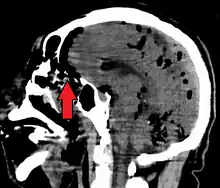

Pneumocephalus is the presence of air or gas within the cranial cavity. It is usually associated with disruption of the skull: after head and facial trauma, tumors of the skull base, after neurosurgery or otorhinolaryngology, and rarely, spontaneously. Pneumocephalus can occur in scuba diving, but is very rare in this context.